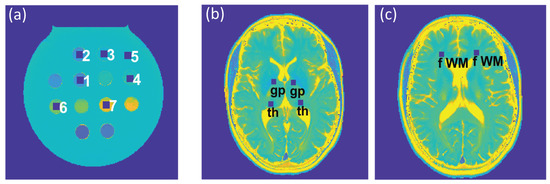

To assess the feasibility of undersampling, regression and Bland–Altman plot analyses were performed for every undersampling factor. T2 and T2* derived from CS-reconstruction of the undersampled data were benchmarked against T2 and T2* obtained from CS-reconstruction of the reference data (Rextra = 1). For analysis of the phantom study, seven ROIs (size = 9 × 9 pixels) were placed within the phantom (Figure 2a), corresponding to the position of the plastic tubes containing the varying iron concentrations. For analysis of the T2 and T2* maps obtained from healthy volunteers, six ROIs (size = 7 × 7 pixels) were selected for each subject, which were placed within the following anatomical brain regions: the globus pallidus, thalamus, and frontal (periventricular) white matter, in both, the left and right hemisphere (Figure 2b,c). For analysis of the T2 and T2* maps obtained from the patient cohort, eight ROIs (size = 7 × 7 pixels) were selected to cover MS lesions identified in four patients.

Figure 2. (a) Regions of interest (ROIs) (size: 9 × 9 pixels), corresponding to tubes with varying iron concentrations in the phantom, which were used for the regression and Bland–Altman plot analyses and the calculation of the median absolute percentage error (MAPE). (b,c) ROIs (size: 7 × 7 pixels) used for further analysis of the in vivo study involving healthy volunteers were placed within the globus pallidus (gp) and thalamus (th) (b) and periventricular frontal white matter (fWM) (c), in the left and right hemispheres.